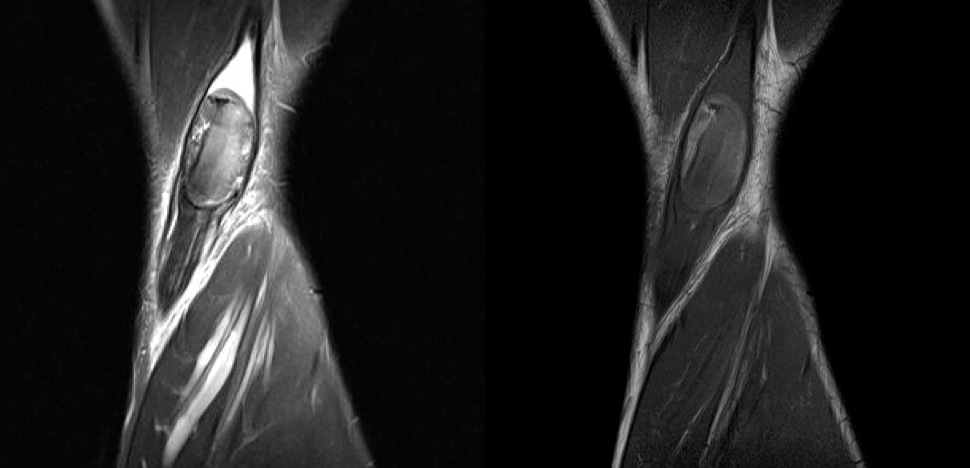

Figure 2 for case Hematoma

Figure 2

Discussion

Semitendinous muscle tear with hematoma

Diagnosis

Hematoma